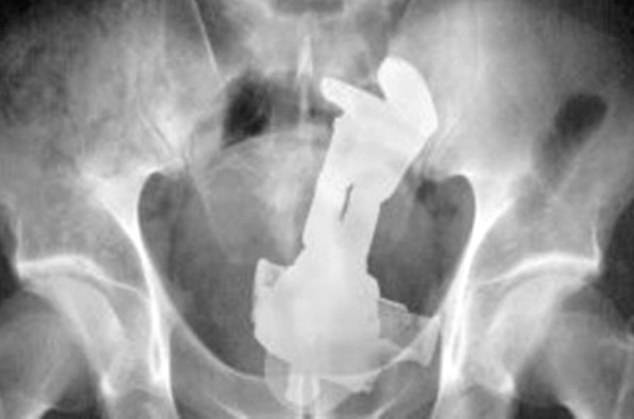

It was found that the rectum is the most common place for bizarre items to get stuck. Some of the objects include household items such as aerosol can, plastic pill bottle, beer bottle, and a plastic cigar holder.

Other articles such as a ‘leg of a telescope’, ‘cell phone’ and ‘Christmas ornament ball’ have also been found in some patients.